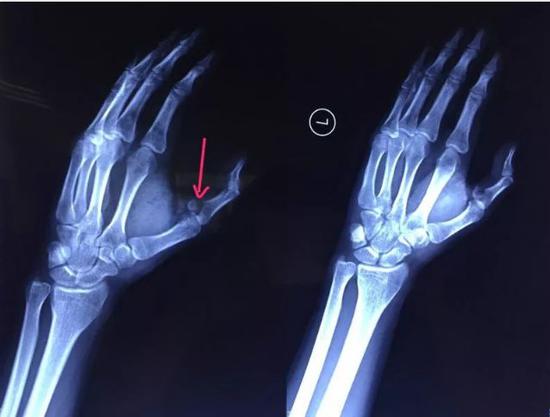

去到医院经过X光检查发现骨折,小袁的左手拇指近节指骨,当晚10点,医生给小袁进行手术,手术历时 2小时顺利完成,石膏固定术后,小袁的左手需采用4~6周